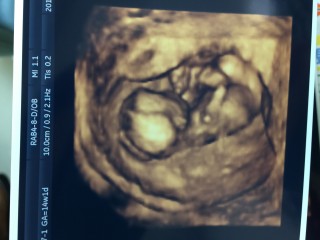

今日ゎ初めての経腹エコーでした。 経腹エコーって事で、午前中仕事休んで旦那サマも一緒に来てくれたのぉ♪♪ いつもゎ動いてくれないんだけど、、、パパもいたからか、おしゃぶりしたり、可愛らしい動きいっぱいしてくれました(´艸`) 順調に成長してて一安心!!!!!! あ~早く性別知りたいなぁぁフフフ

指をおしゃぶり中♪まだ性別はわかりません。胎盤が少しわかるようになってきたと先生が。今の所順調です。